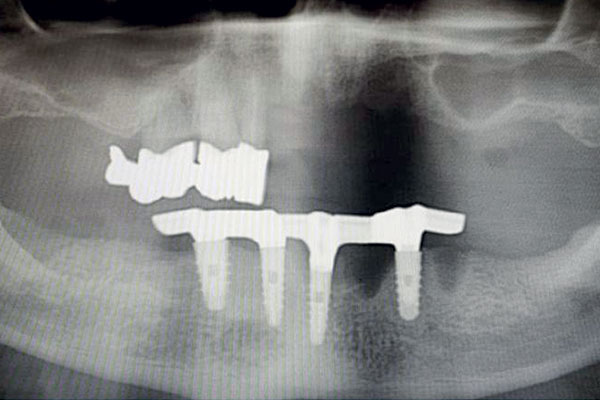

È una protesi completamente rimovibile e personalizzata, la cui stabilità è garantita dal posizionamento sull’arcata da riabilitare di due o quattro impianti collegati tra loro eventualmente da una barra. La protesi risulterà stabile perché agganciata proprio agli impianti o alla barra con attacchi particolari.